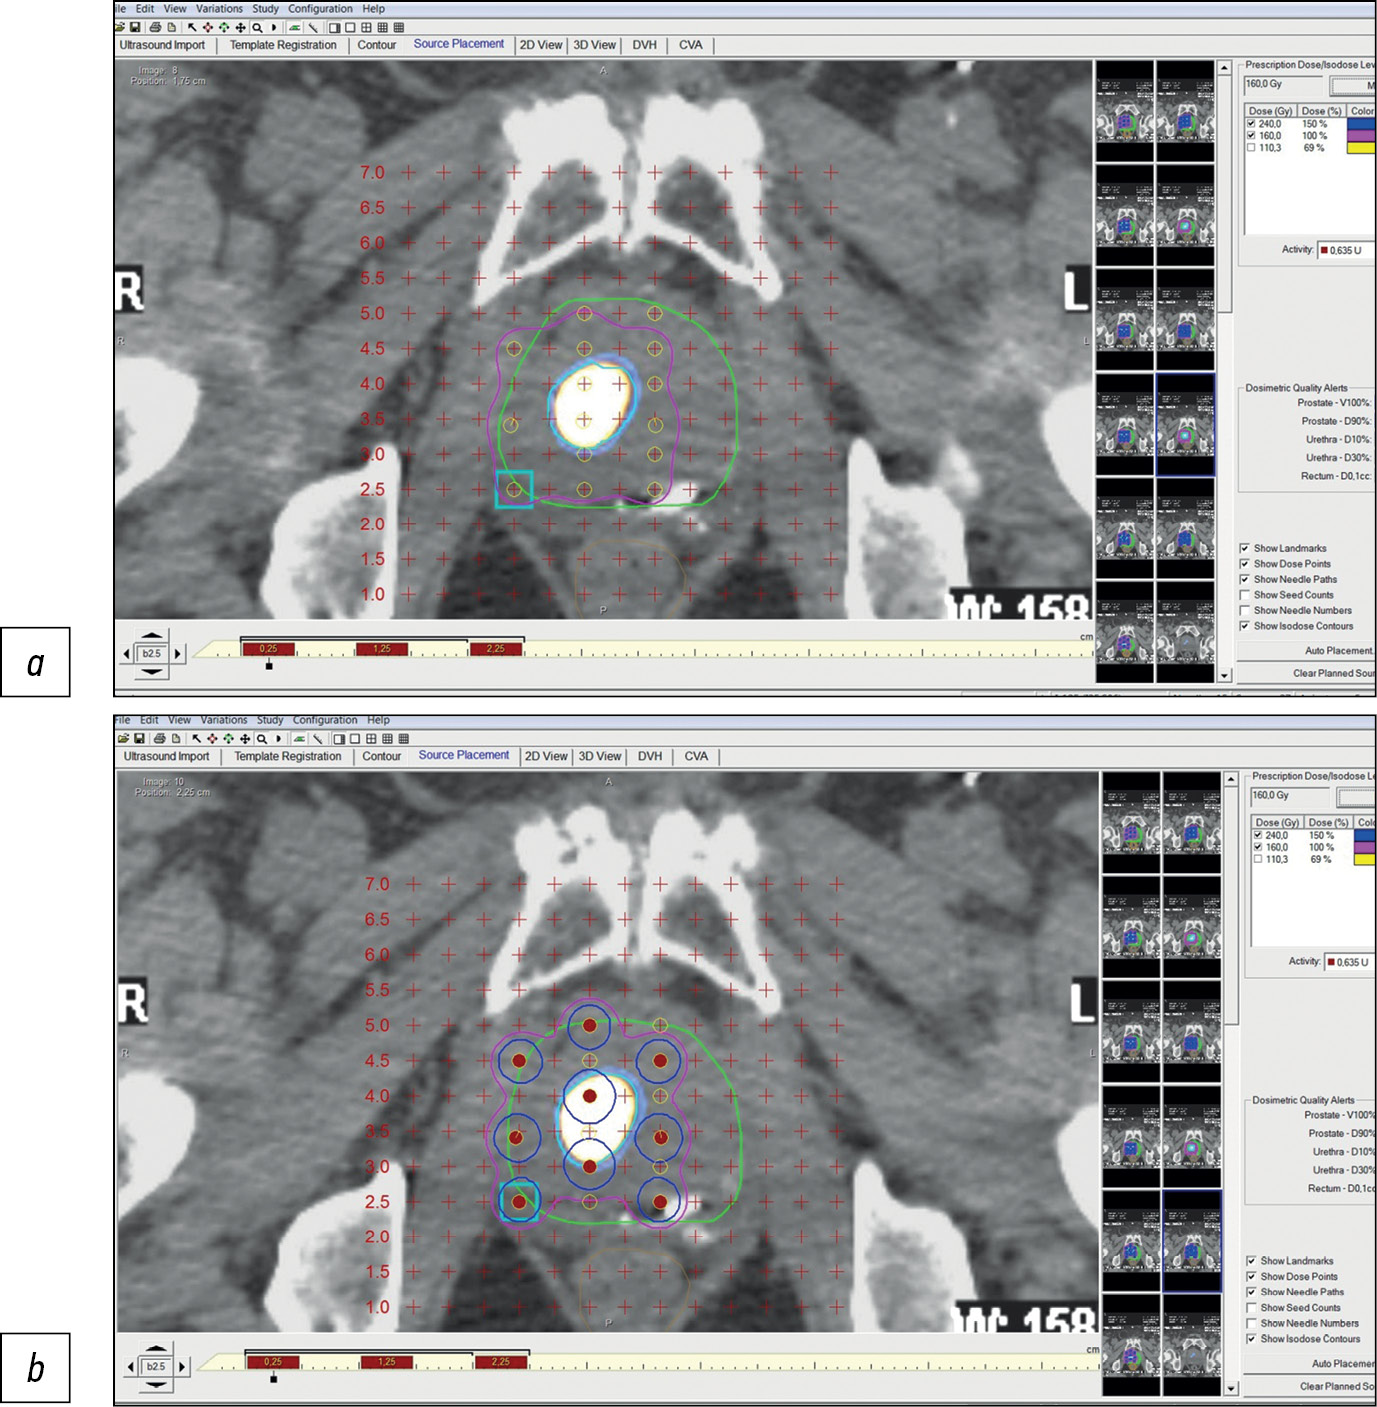

Figure 1 shows an example of pre-implantation brachytherapy planning using 125I sources. Crosses indicate virtual holes in the stereotactic array, which fully corresponds to the array implanted in a patient. Red dots indicate microsources, whereas colored lines indicate isodose distribution.

Fig. 1. Stages of dosimetry planning of brachytherapy localized prostate cancer using 125I microsources considering SPECT/CT with 99mTc-HYNIC-PSMA: (a) topometric marking and (b) topometric marking and dosimetry planning of brachytherapy.